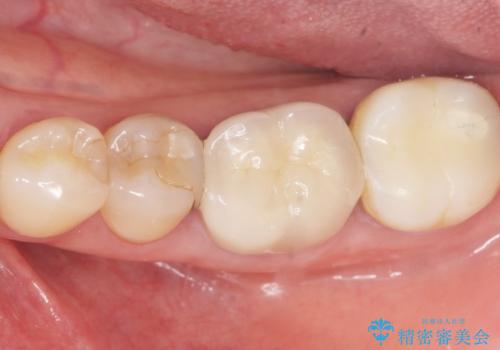

- 詰め物の境目が黒いことを気にされ、来院された患者様です。

精査したところ、左下の奥歯(左下5)のプラスチックの詰め物と歯の境目が虫歯になり、黒くなっていました。